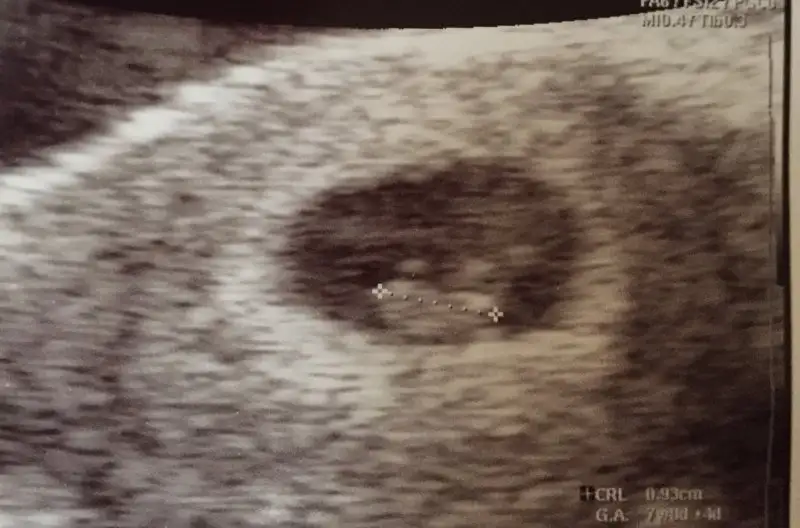

Arkadaşlar lütfen bi bakın bi yorumlayınn. Çok merak ediyorum.Vajinal usg. Tahminiz nedir. Şimdiden teşekkürler.

Kız gibi canım Rabbim sağlıklı sıhhatli hayırlı evlat nasip etsinArkadaşlar lütfen bi bakın bi yorumlayınn. Çok merak ediyorum.

Çok teşekkür ederim. Sağlıkla sıhhatle gelsin. Bu da 7 haftalık karından usg kız mı acaba gerçektenKız gibi canım Rabbim sağlıklı sıhhatli hayırlı evlat nasip etsin